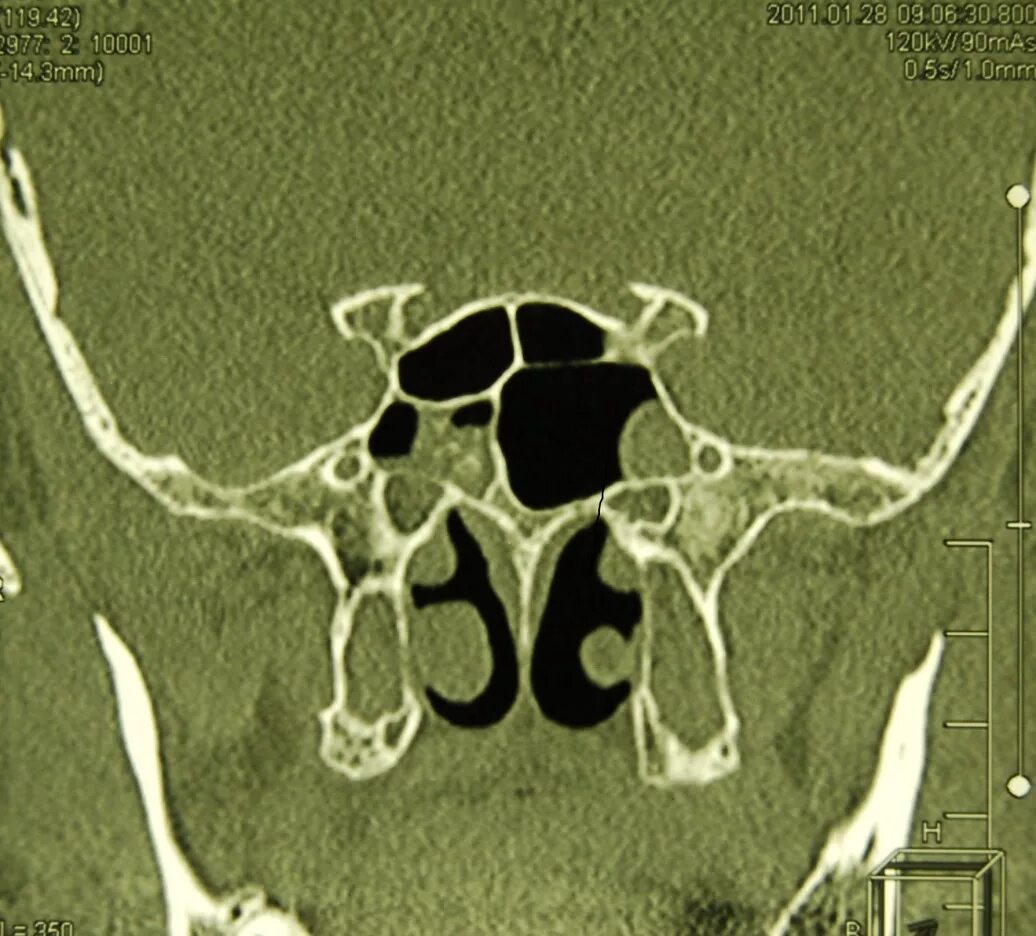

Сфеноидит симптомы у взрослых